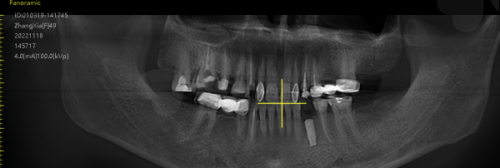

种植牙种的种植步骤通常较为复杂。首先是术前检查和评估,医生会对患者的口腔进行全方面检查,包括拍摄X光片、CT等,了解牙槽骨的情况、牙齿缺失部位等,以确定患者是否适合种植牙种。接着进行种植体植入手术,在局部麻醉下,将种植体植入牙槽骨内。这一过程需要医生有精细的操作,确保种植体的位置和角度合适。植入后需要等待一段时间让种植体与牙槽骨形成骨结合,这个时间一般为3 - 6个月。末尾进行牙冠安装,经过检查确认种植体与牙槽骨结合良好后,就可以安装合适的牙冠,完成整个种植牙种过程。